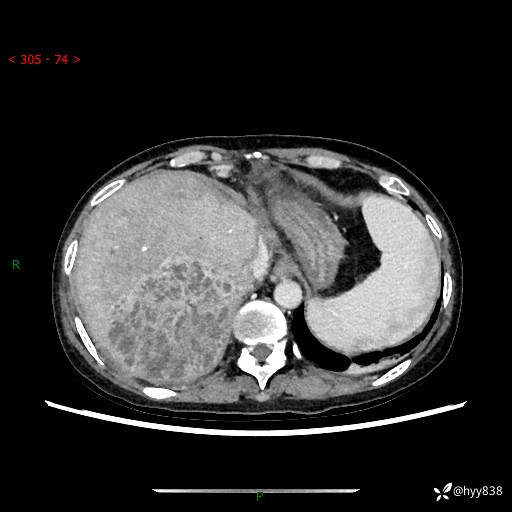

上腹部CT平扫